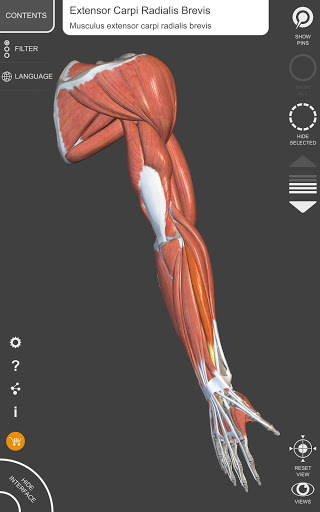

"Anatomy 3D Atlas" cho phép bạn nghiên cứu giải phẫu người theo cách dễ dàng và tương tác.

Thông qua giao diện đơn giản và trực quan, bạn có thể quan sát mọi cấu trúc giải phẫu từ mọi góc độ.

Các mô hình giải phẫu 3D đặc biệt chi tiết và có kết cấu lên đến độ phân giải 4k.

• Hệ thống cơ xương

• Hình dung các cơ qua các lớp từ lớp nông đến lớp sâu nhất

• Mô tả các cơ: nguồn gốc, chèn, chi phối thần kinh và hành động